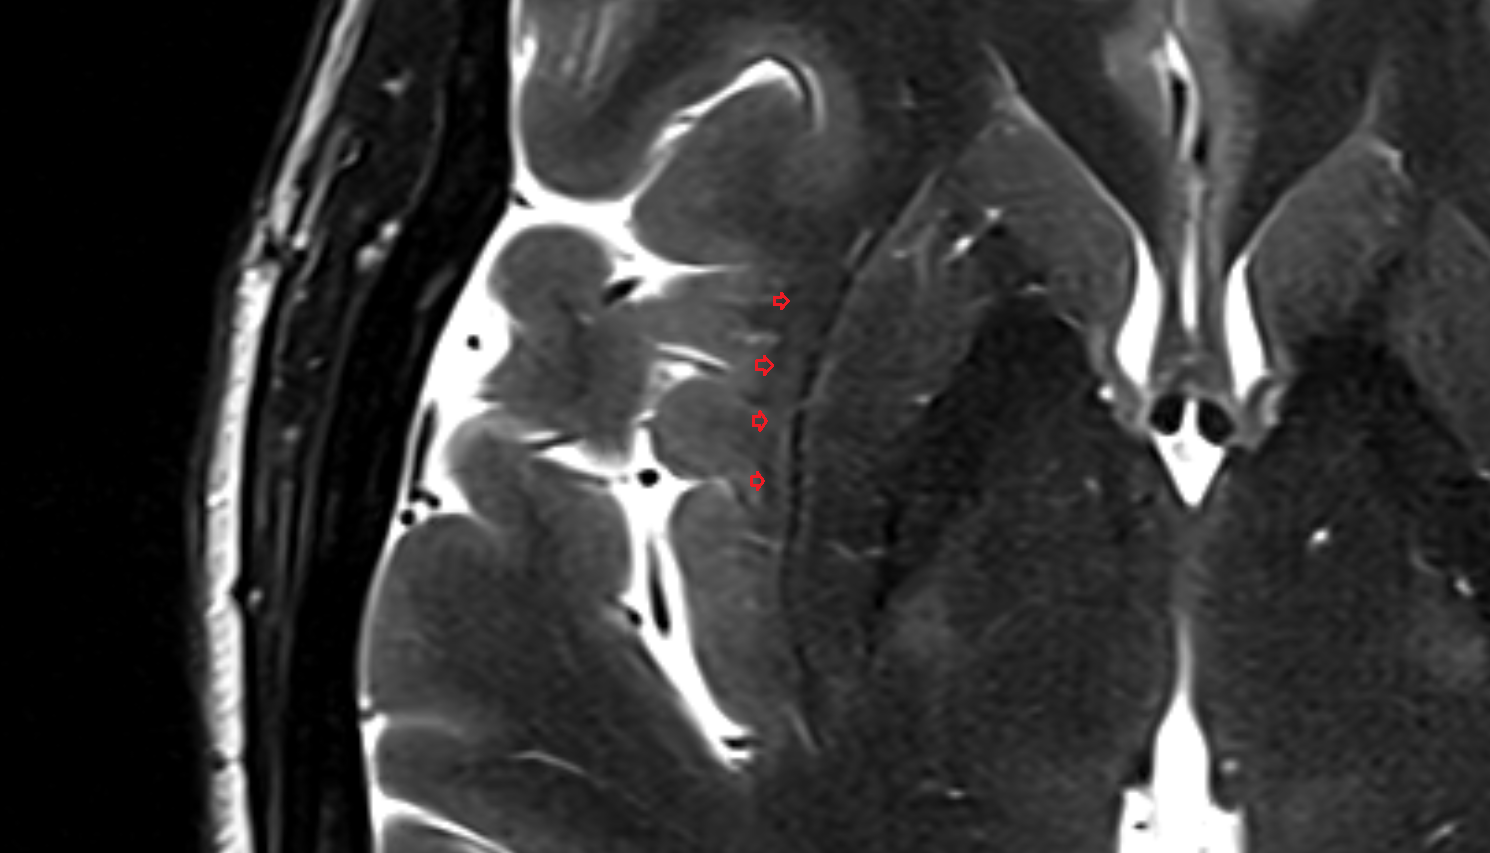

- Central lobule (II & III) of Cerebellum

- Culmen (IV, V) of Cerebellum

- Declive (VI) of Cerebellum

- Folium (VII) of Cerebellum

- Tuber of vermis (VII)

- Pyramid of vermis (VIII)

- Uvula of vermis (IX)

- Nodule of vermis (X)

- Cerebellar tonsil (H IX)